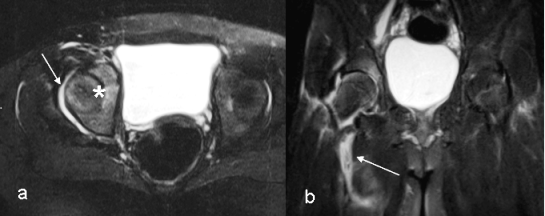

Si � iniziato un trattamento con Ibuprofene nell'ipotesi diagnostica di artrosinovite transitoria dell'anca. Dopo 48 ore M.I. presentava febbre elevata e persistenza della sintomatologia dolorosa, sebbene in parte attenuata. La ripetizione degli indici di flogosi dimostrava un notevole aumento della PCR, superiore a 300 mg/l, e del TAS 1115 UI/mg. Progressivo aumento delle piastrine (737.000/mmc) e dei globuli bianchi a 21.000 / mmc. Il dosaggio degli anticorpi antinucleo � risultato non significativo. L'emoculture sono risultate sterili. Per il rifiuto dei genitori all'artrocentesi, � stata praticata la RM del bacino con il riscontro di versamento intrarticolare nella coxofemorale destra, raccolta fluida tra i ventri muscolari del pettineo e dell'ileopsoas ed associato edema interspongioso nell'ambito della testa del femore e dell'acetabolo omolateralmente (Figura 1, a e b). La diagnosi formulata � stata di piomiosite.

Il reperto della RM, grazie all'utilizzo di sequenze sensibili alla identificazione delle componenti idriche dei tessuti (FSE T2 fat-sat), ci ha permesso di formulare la diagnosi di piomiosite pelvica con interessamento dei muscoli ileopsoas e pettineo5.

Figura 1. a) RM, Assiale FSE T2 Fat-sat: Versamento intra-articolare nell'ambito dell'articolazione coxo-femorale di destra (freccia). Incremento di segnale della testa femorale e dell'acetabolo di destra, rispetto all'arto controlaterale, da riferire ad edema intraspongioso (asterisco).

b) RM, Coronale FSE T2 Fat-sat: Edema e versamento a carico dei ventri muscolari del pettineo e dell'ileo-psoas (freccia).